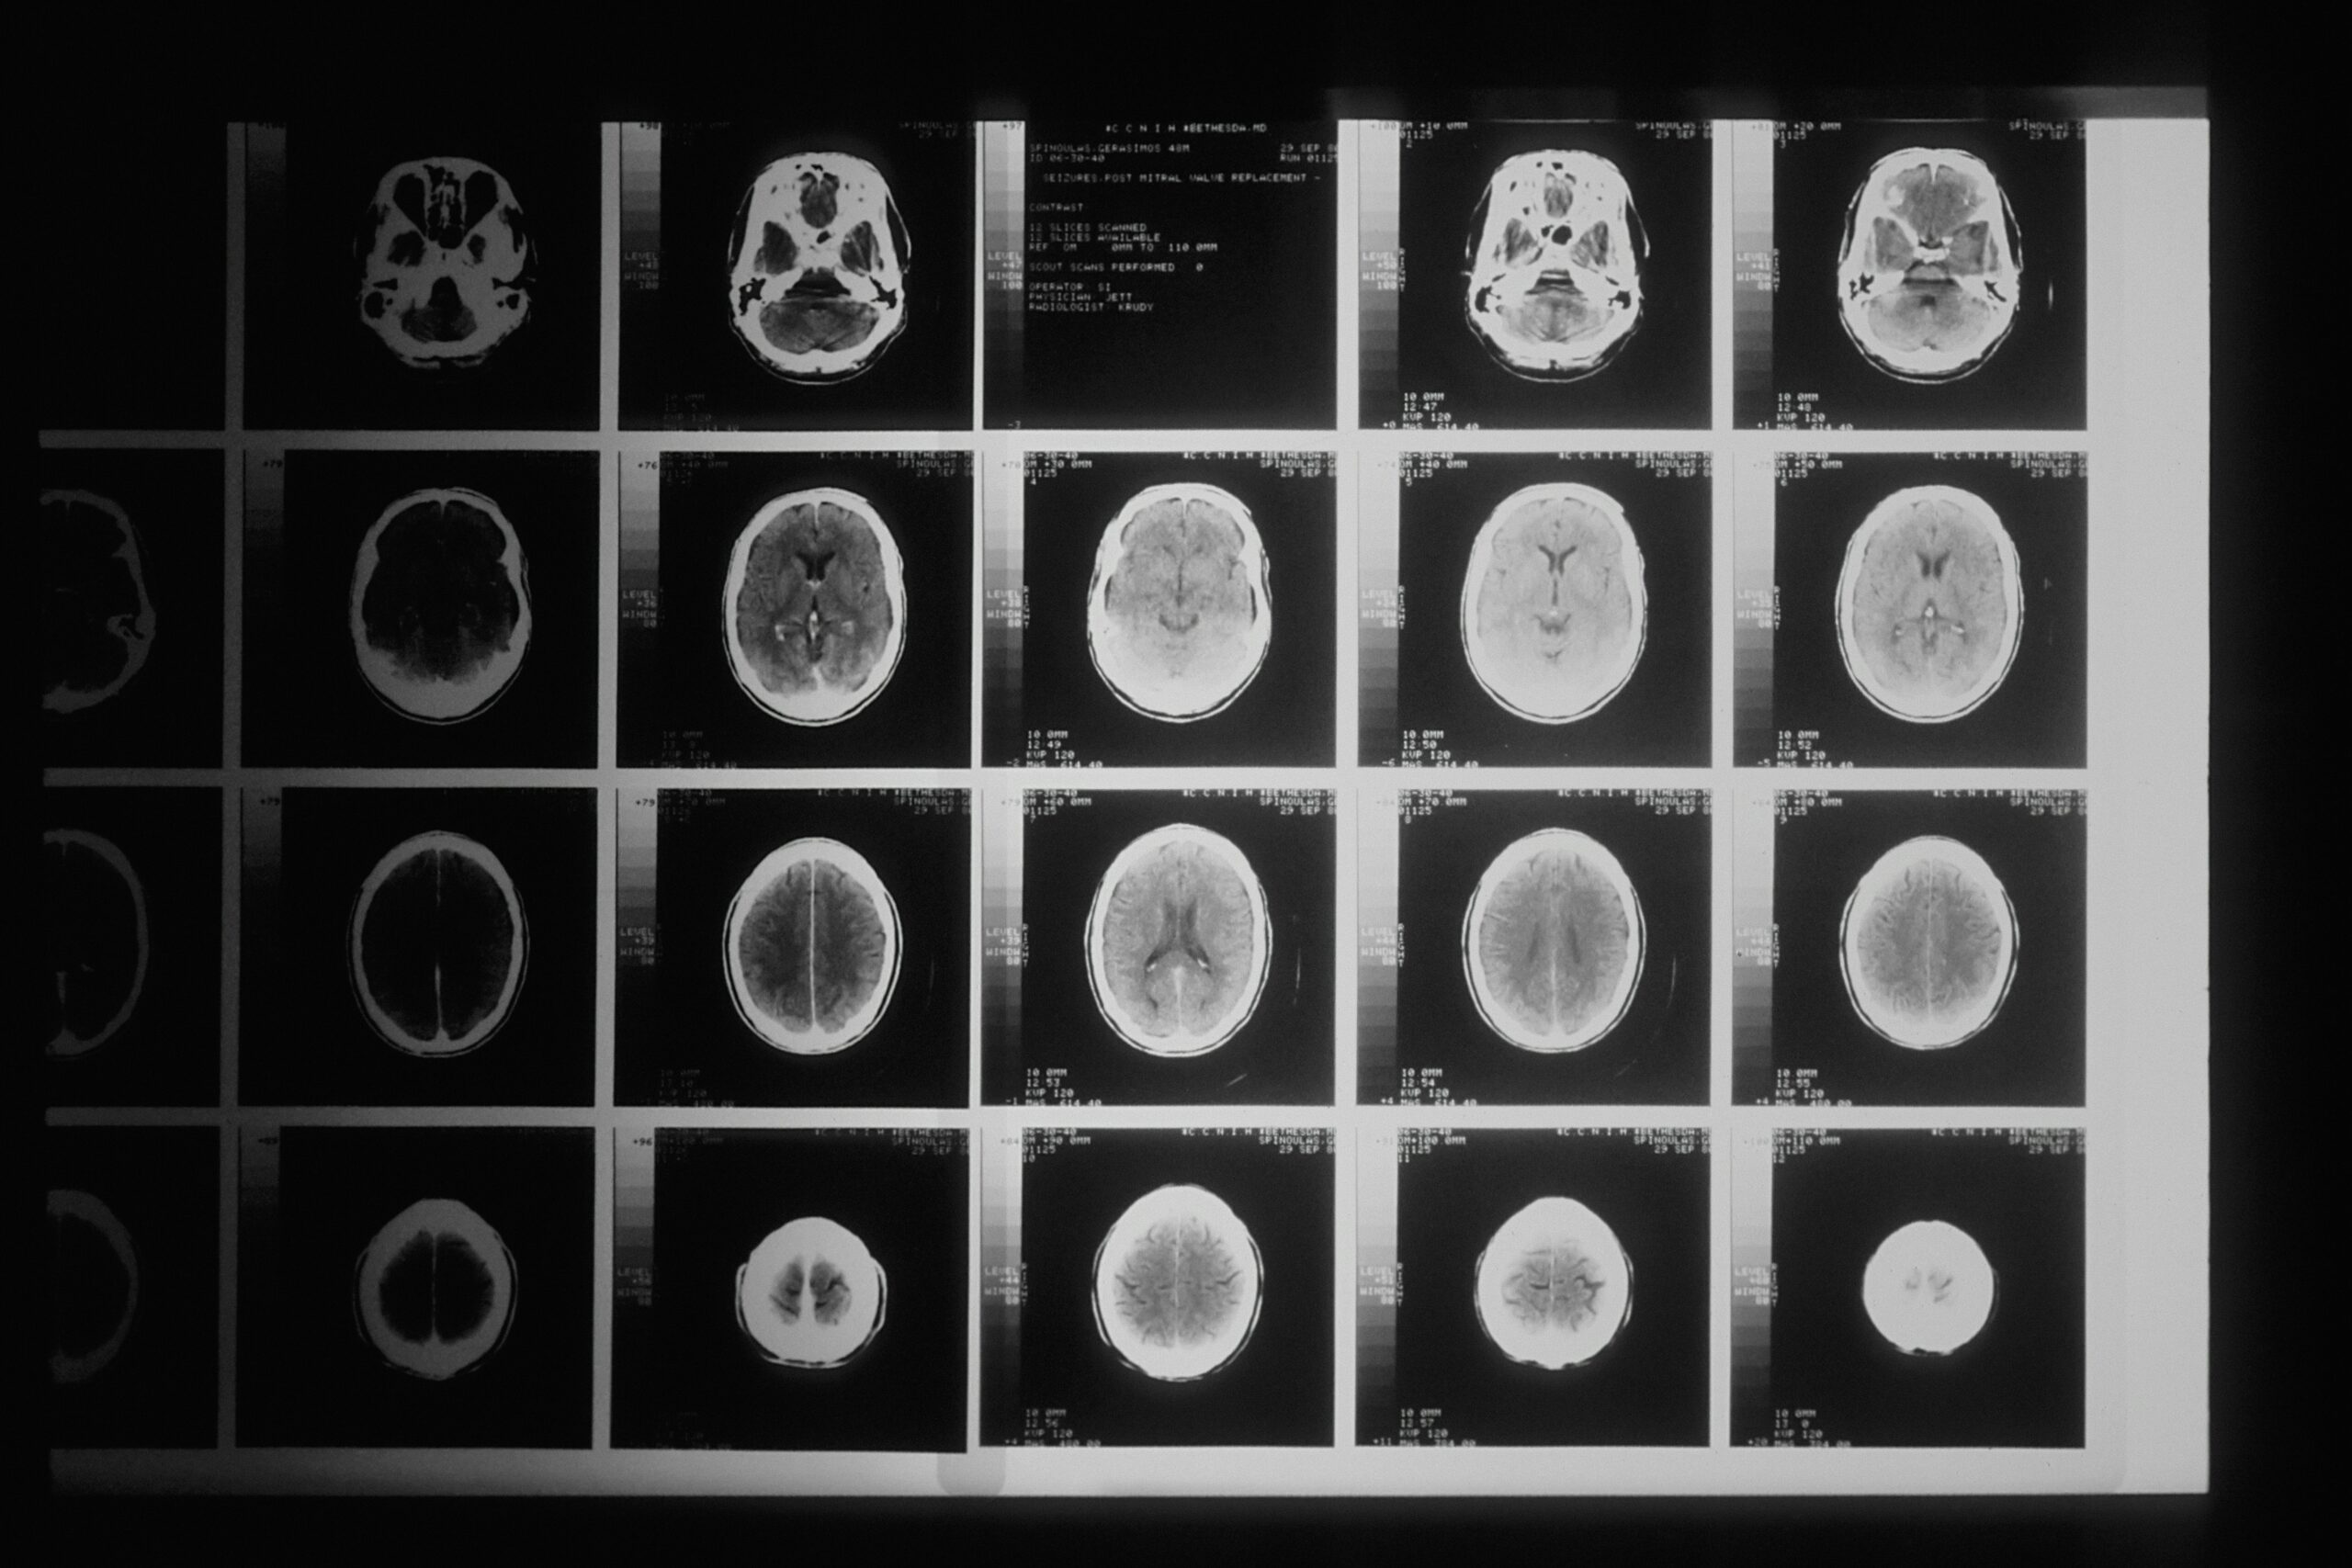

研究報告指出,癌細胞就像寄生蟲會分泌酵素,破壞組織結構以利入侵,同樣會釋放基質金屬蛋白酶(MMP)溶解細胞外的支撐結構,為轉移開路。且如同寄生蟲挑選宿主最脆弱的部位寄生,癌細胞也偏好肺、肝、腦、骨頭等營養充足且免疫監控較弱的器官,彷彿在為自己尋找一間「最舒適的房子」。